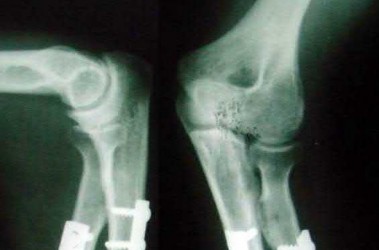

What physical exam finding is most likely to be found in association with the injury shown in Figures A and B?

The x-ray shows a fracture of the anteromedial facet of the coronoid with an intact radial head. Large anteromedial facet fractures are associated with varus posteromedial rotatory instability.

The anteromedial facet of the coronoid provides support to the medial elbow against varus stress. Varus and posteromedial force applied to the elbow results in disruption of the lateral collateral ligament (LCL) from its proximal origin. The coronoid is fractured as it is forced against the medial trochlea.

Coronoid fractures of significant size involving the sublime tubercle (insertion of medial collateral ligament) result in varus instability.

Steinmann reviews the anatomy, diagnosis, classification and treatment of coronoid fractures with a focus on surgical exposures and fixation techniques. He states that when a coronoid fracture is associated with a pattern of varus instability, it requires fixation with either suture, buttress plating or screw fixation. Concomitant LCL repair or reconstruction will also be necessary.

Doornberg et al. reviewed 67 coronoid fractures to determine whether type of coronoid fracture correlated with pattern of instability. They found strong

associations between (1) large coronoid fractures and trans-olecranon fracture-dislocations, (2) small fractures and terrible-triad injuries, and (3) anteromedial facet fractures and varus posteromedial rotational injury mechanisms.

Doornberg et al. evaluated 18 patients with a fracture of the anteromedial facet of the coronoid. They found that malalignment of the anteromedial facet fragment was associated with arthrosis and a fair or poor result.

Figure A is an AP view of an elbow with an anteromedial facet of the coronoid fractured. The lateral joint space is widened due to injury to the LCL. The medial joint space is narrowed and collapsed. A lateral view is shown in Figure

B. Illustrations A and B show AP and lateral views of a coronoid fracture fixed with buttress plating. The LCL origin was fixed with a suture anchor. Illustration C shows the O'Driscoll classification of coronoid fractures. Illustration D lists injury patterns that suggest posteromedial versus posterolateral rotatory instability.